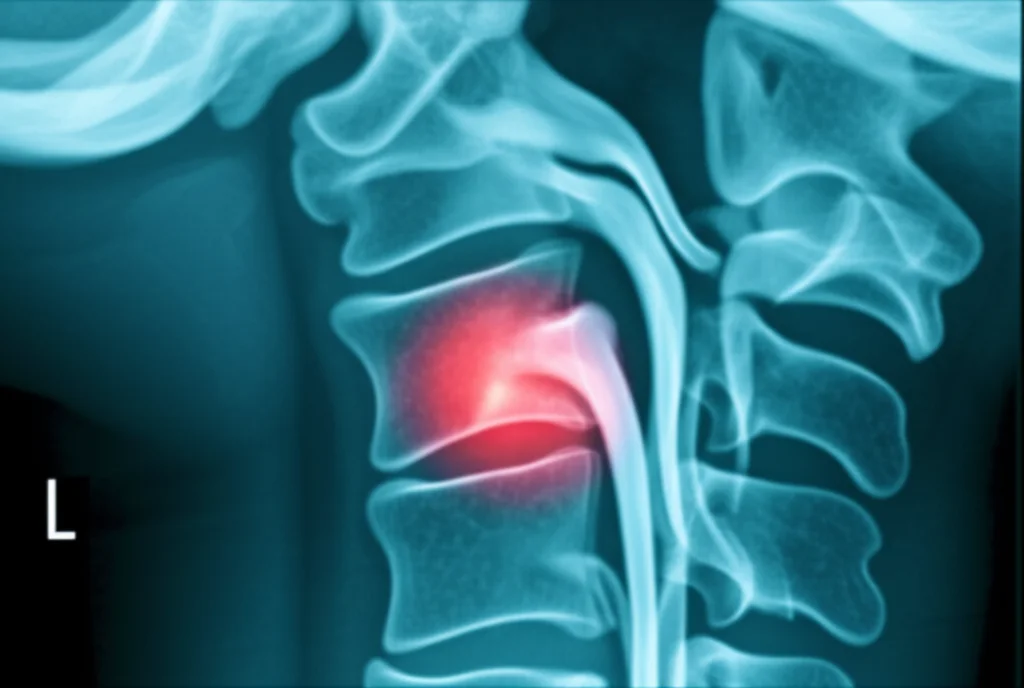

Prima di tuffarci nei risultati, capiamo di cosa stiamo parlando. La mielopatia cervicale degenerativa (DCM) è una condizione un po’ antipatica in cui il midollo spinale nel tratto cervicale (il collo, per intenderci) viene compresso. Questa compressione può derivare dall’artrosi, da ernie discali o dall’ispessimento dei legamenti. I sintomi? Possono variare da dolore e rigidità del collo, a problemi di equilibrio, difficoltà nella deambulazione, perdita di destrezza nelle mani e, nei casi più seri, problemi con la funzione intestinale o vescicale. Insomma, una bella gatta da pelare che impatta pesantemente sulla qualità della vita.

L’intervento chirurgico più comune per decomprimere il midollo è la laminectomia, che consiste nella rimozione di una piccola porzione dell’osso vertebrale (la lamina) per dare più spazio al midollo. A volte, a questa procedura si associa una stabilizzazione con viti e barre (fissazione posteriore). Ora, la domanda sorge spontanea: un paziente di 80 anni o più può affrontare un intervento del genere e trarne beneficio come un paziente più giovane?